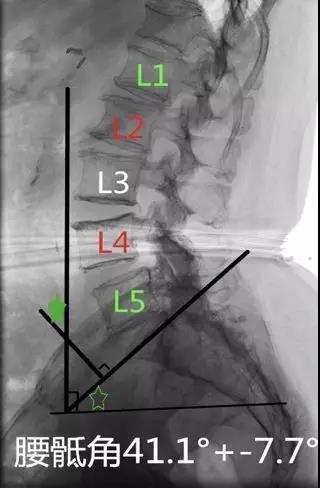

- 腰骶角(lumbosacral angle):

- 腰椎纵轴和骶椎纵轴之间的夹角;

- S1上缘连线与水平线的交角。正常值为41.1°±7.7°or34°(亦称骶骨水平角)。

临床意义:增大提示有滑脱进展风险。成人若>45°则可称水平骶椎,腰骶角增大时腰椎前凸加深和骨盆前倾,导致骶髂关节劳损,腰脊柱力平衡失调,并继发腰、胸、颈段劳损称之为“水平骶椎综合症”。